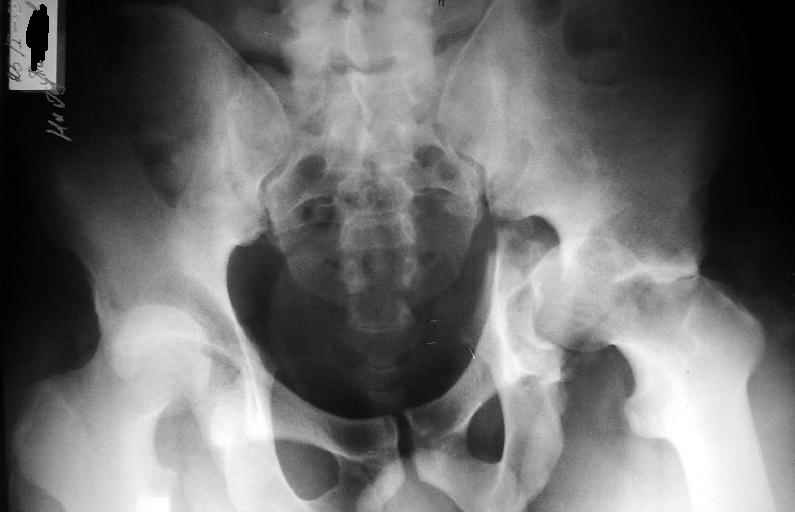

Пациент переведен в нашу клинику на 5 день после множественной травмы 25.01.2003 - двустороннее повреждение вертлужных впадин, разрыв левого крестцово-подвздошного сочленения. Вывихи обоих бедер. В месте первичного поступления подвздошный вывих правого бедра вправлен 26.01.2003, наложено вытяжение за левую вертельную область. Остеосинтез левой вертлужной впадины выполнен у нас 6.02.2003. Вопрос: надо ли синтезировать задне-верхний край правой вертлужной впадины?

правую впадину собрали здорово! Мои поздравления Рункову. Сами меня учили-учили, а где же запирательная проекция левой вертлужной

впадины. Такое впечатление что на КТ есть интерпозиция кусочком, тогда уж точно надо туда залесть, а так, я считаю не стоит.

Уважаемый Алексей, через месяц после повреждения обострять травму, чтобы продлить "колясочный" срок? Второй сустав станет опорным не скоро.Головка на Ртг концентрически вставлена, задний фрагмент не интерпонирует, лимбус,по видимому тоже, ямочный фрагмент мешать не должен,герметизирующую манжету адекватно восстановить, обычно, не удается. Выгоды от оперативного вмешательства сомнительны. Я бы оперировать не стал.Еще месяц без нагрузки (по меньшей мере) и в нашей "конторе"- МОНИКИ(Вы наверняка знаете О.Ш.Буачидзе) положились бы на ощущения пациента при активных движениях правым бедром. Можно и сейчас проверить на возможность блокады и тогда принимать окончательное решение.